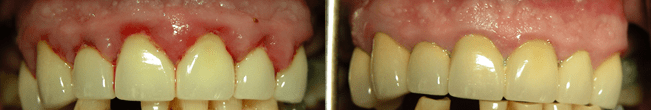

Paciente con pérdida de hueso y raspado dental de la infección con cureta, cuidado de las encías sangrantes

Las personas con problemas especiales o con riesgo de padecerlos necesitan que se les realice uno o varios Raspados o también llamados Curetajes. Esta es una técnica especializada que elimina la infección de la profundidad de la bolsa, llegando a zonas no visibles, muy importante para el correcto cuidado de las encías sangrantes. Necesita un alto nivel de especialización porque a menudo se trabaja a ciegas y en espacios muy pequeños, en donde el tacto de la persona bien entrenada es la única arma para eliminar de manera efectiva los irritantes bacterianos. El raspado dental bien hecho disminuye drásticamente el sangrado de encías de manera inmediata. Al acabar el curetaje siempre hacemos un Alisado Radicular para dejar la superficie del diente menos receptiva a las bacterias.